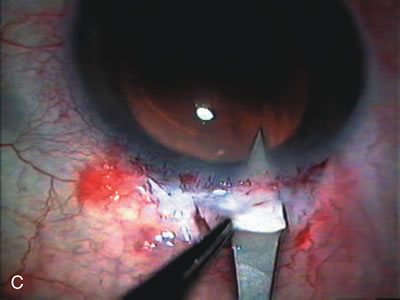

CATARACT EXTRACTION ALONE REDUCES IOP IN MOST EYES WITH ANGLE-CLOSURE GLAUCOMA

Uncomplicated cataract extraction substantially reduces IOP, along with the number of postoperative glaucoma medications in eyes with angle-closure glaucoma.146,147 When preoperative gonioscopy reveals PAS, along with adjacent areas of appositional closure, lens extraction alone in select cases may be a reasonable alternative to filtration surgery.148,149 Phacomorphic angle-closure disease due to enlargement of the lens with progressive angle crowding is eliminated following lens extraction. The width and depth of the anterior chamber angle in eyes with angle-closure glaucoma increases significantly after cataract extraction with IOL implantation and becomes similar to open-angle glaucoma and normal eyes.150,151 (Fig. 5). Combining phacoemulsification, IOL implantation, and limited goniosynechialysis is effective in the treatment of cataract and chronic angle-closure glaucoma.152 Phacoemulsification with implantation of a foldable IOL is more effective in reducing IOP and improving visual acuity than surgical peripheral iridectomy in eyes with acute angle-closure glaucoma.153

Fig. 5. Anterior chamber angle changes associated with lens extraction and PCIOL This 65-year-old Vietnamese woman has a long-standing history of chronic angle-closure glaucoma treated with laser peripheral iridectomy. The optic nerve demonstrated mild glaucomatous damage and IOP was moderately controlled on two antiglaucoma medications. The cataract was removed through temporal clear corneal phacoemulsification with foldable acrylic IOL. A. Symptomatic cataract in narrow-angle glaucoma eye with patent iridectomy. B. Intraoperative goniophotograph showing crowding of angle with increasing narrowness due to phacomorphic component. C. Intraoperative photograph showing temporal clear corneal approach with IOL in the capsular bag. D. Intraoperative goniophotograph demonstrating deepening of chamber angle following lens extraction. Proposed theories for IOP reduction following lens extraction with complete wound closure: